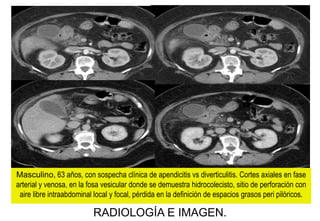

Masculino, 63 años, con sospecha clínica de apendicitis vs diverticulitis. Cortes axiales en fase

arterial y venosa, en la fosa vesicular donde se demuestra hidrocolecisto, sitio de perforación con

aire libre intraabdominal local y focal, pérdida en la definición de espacios grasos peri pilóricos.

IMPRESIÓN TOMOGRÁFICA:

COLECISTITIS CRONICA

ALITIASICA AGDIZADA.

QUIRÚRGICO:

PERFORACION ULCERA

PILORICA.

Masculino, 63 años, con sospecha clínica de apendicitis vs diverticulitis..